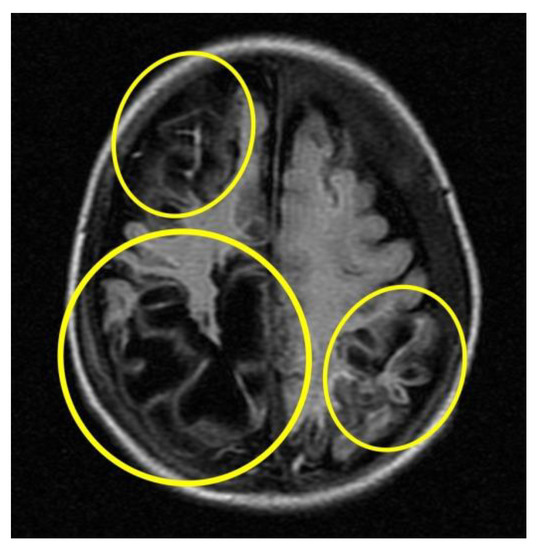

Subsequent instrumental investigations were performed on the baby to assess cranio-encephalic outcomes. In particular, the MRI (Figure 5) performed about a month after the presumed trauma revealed a picture characterised by cortical atrophy and cystic evolution of the brain parenchyma, mainly in the occipital region bilaterally.

Figure 5.

MRI cortical atrophy and cystic evolution of the brain parenchyma (circles in yellow).